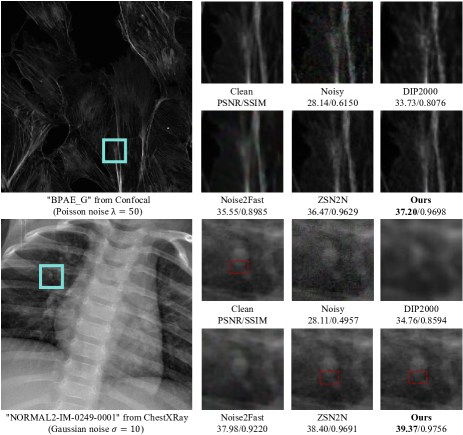

Table II presents the results on the Set14 and BSD68 datasets, where our LoTA-N2N consistently outperformed other methods across all evaluated noise levels. Furthermore, our methodology has shown promising results in the biomedical domain, as evidenced by the performance metrics presented in Table III, which include analyses on both confocal and X-ray datasets. In addition to its enhanced denoising capabilities, our model further distinguishes itself through significantly reduced computation time. These attributes collectively exemplify an advantageous synergy of performance efficacy and computational expediency. Additionally, Figure 5 presents a visual comparison on confocal and X-ray datasets, with the most significant differences highlighted within cyan line boxes. The upper section demonstrates the results on the confocal dataset, wherein our approach delivers the clearest detail and texture without introducing artifacts observed in approaches like Noise2Fast. Compared with the ZSN2N method, our technique preserves the finest features, particularly at the center of the display frame, demonstrating superior restoration capabilities. The lower portion illustrates the results on a pulmonary X-ray dataset. Here, the ZSN2N method unfortunately introduces spurious texture structures not present in the original image, as indicated by the red dashed-line boxes. In contrast, DIP and Noise2Fast struggle to recover such intricate texture, while our method continues to display robust denoising performance, producing images that most closely resemble the clear samples.